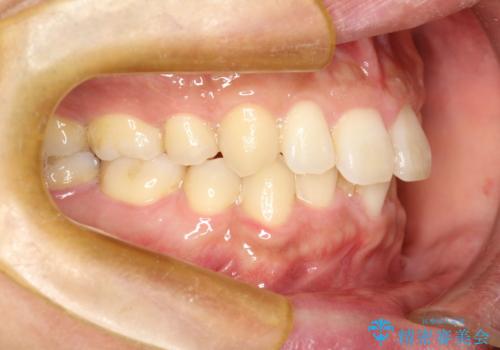

- 以前、上下左右4本抜いてワイヤー矯正をしていた方で、後戻りで下の前歯のガタガタを気にして来院されました。

マウスピース矯正にて、下の歯はIPR(歯と歯の間を削る)を入れることでガタガタの改善、咬み合わせの深さも改善をはかる治療計画をたてました。

歯と歯の間を削って隙間を作って矯正をしています。

保定装置(後戻り防止のための装置)は、基本的にはマウスピースタイプをお渡ししているのですが、患者様のご希望で取り外ししないタイプを希望されたので、前歯の裏側を細いワイヤーで固定(ボンディングリテーナー)を作成しています。